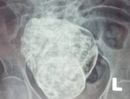

Bệnh sởi chưa có dấu hiệu chững lại, Cục Y tế dự phòng (Bộ Y tế) vừa đưa ra khuyến cáo: bệnh sởi đã được ghi nhận ở 59/63 tỉnh, thành phố với trên 5.000 ca mắc.